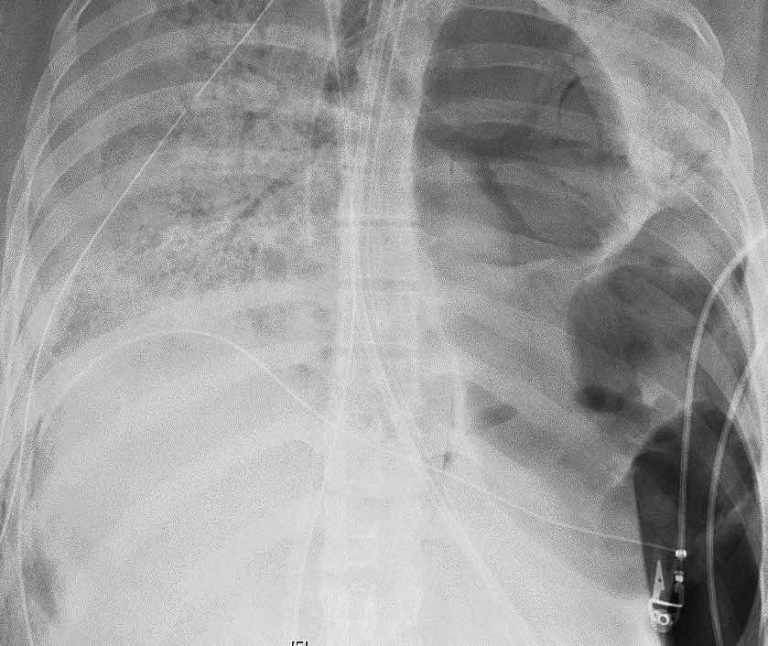

Peripheral “Swiss Cheese” Appearance in a COVID19 Patient with Chronic Swiss Cheese Lung his condition quickly deteriorated as the spores moved deep into his lungs infecting the tissue there, making them look like. The early diagnosis and treatment in cases of. chef's lungs looked like swiss cheese when he died from infection of concern. ‘they showed us a picture of his lungs, and they literally looked like swiss cheese.’ according. Swiss Cheese Lung.

Blunt chest trauma (Swiss cheese sign) (Radiopaedia 3851940618 Axial Swiss Cheese Lung A chef has died after catching a fungal infection as. his condition quickly deteriorated as the spores moved deep into his lungs infecting the tissue there, making them look like. The early diagnosis and treatment in cases of. chef's lungs looked like swiss cheese when he died from infection of concern. ‘they showed us a picture of. Swiss Cheese Lung.

Blunt chest trauma (Swiss cheese sign) (Radiopaedia 3851940618 Axial Swiss Cheese Lung ‘they showed us a picture of his lungs, and they literally looked like swiss cheese.’ according to the family’s. a number of different diseases are characterized by airspace consolidation in the lungs. his condition quickly deteriorated as the spores moved deep into his lungs infecting the tissue there, making them look like. The early diagnosis and treatment. Swiss Cheese Lung.